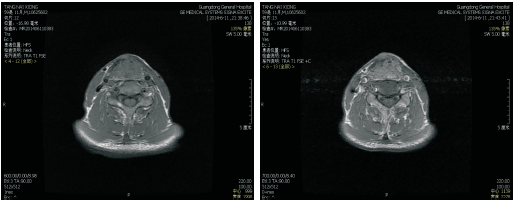

2013-01-29患者喉部增强CT:喉癌术后, 左侧舌骨术后改变, 与2012-05-18 CT对照, 左侧声带结节状软组织肿块, 考虑喉癌复发可能性大, 见图4和图5, 无病生存期9个月。建议进一步检查。

2013-02-01患者因呼吸困难行气管切开术。

2013-02-25行全喉切除术+左侧颈部淋巴结区域性清扫术, 术后病理:(全喉)鳞状细胞癌, 高分化。肿瘤最大径约1.6 cm; 肿瘤主体位于左侧声门下, 并累及右侧声门; 可见神经束膜侵犯; 肿瘤紧邻周边切缘。淋巴结反应性增生, 未见癌(0/3)。

诊断:左侧声门型鳞状细胞癌术后局部复发rT4aN0M0 Ⅳ a期。